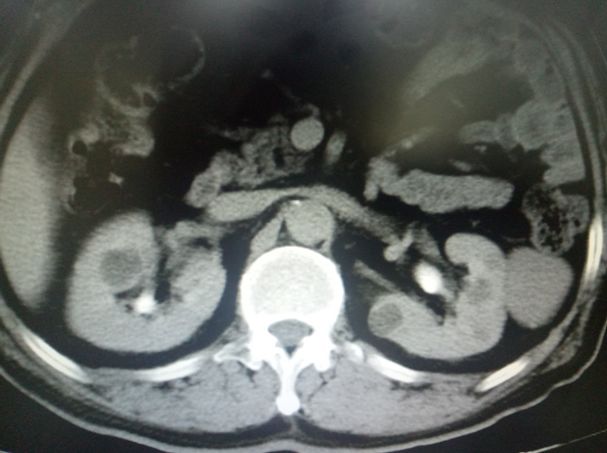

“疼,真疼,疼起来都不好意思说出口。”七十多岁的付大伯说起自己的疼简直苦不堪言。腰酸、腹胀、下腹部及阴囊反复疼痛坠胀……说得通俗点就是“蛋疼”。到杭州市第一人民医院泌尿外科就诊,经主任医师邓刚检查后诊断为双侧肾囊肿,伴双侧的精索静脉曲张,这与付大伯描述的症状相符。

尽管这两个病都是泌尿外科常见病,手术对于邓刚主任医师来说也都是常规操作。如果按常规手术,那么付大爷需要先分别做肾囊肿手术,然后再二次行精索静脉曲张手术,但因为都是是双侧手术,即使采取微创的腹腔镜手术,两边两个手术加起来,总共需要进行的腹腔镜打孔数有9个之多!邓刚主任医师在仔细分析病情、反复研究手术方案后,决定一次手术帮付大伯解决所有问题。他带领团队为付大伯计划并实施了经腹腔镜下双肾侧囊肿去顶减压术+双侧精索静脉曲张结扎术。腹腔镜的手术置孔仅4个,手术顺利。手术中,且发现肾囊肿液炎症浑浊,精索静脉曲张的程度也比较严重,通过手术也予以解决。真可谓“一箭多星除病患”,一箭多星,即用一枚运载火箭同时或先后将数颗卫星送入地球轨道的技术。殊不知,面对复杂的患者病情应对措施,外科手术也能做到“一箭多星”。